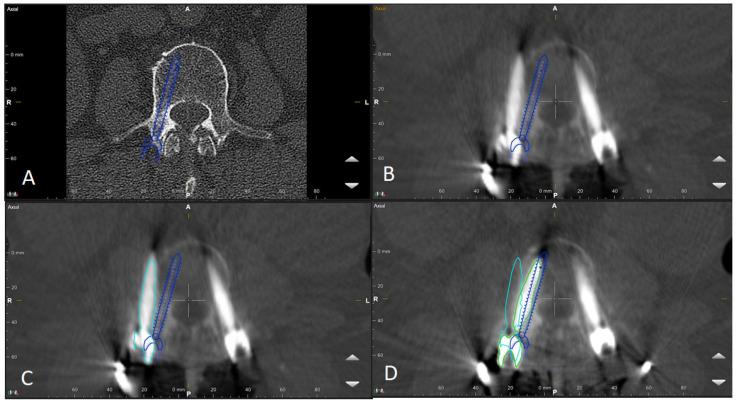

The aim of this study is to present the initiation of robotic-guided (RG) spine surgery into routine clinical care at a single center with the use of intraoperative CT (iCT) automatic registration-based navigation. The workflow included iCT with automatic registration, fusion with preoperative imaging, verification of preplanned screw trajectories, RG introduction of K-wires, and the insertion of pedicle screws (PSs), followed by a control iCT scan. All patients who underwent RG implantation of pedicle screws using the Cirq robotic arm (BrainLab, Munich, Germany) in the thoracolumbar spine at our department were included in the study. The accuracy of the pedicles screws was assessed using the Gertzbein-Robbins scale (GRS). In total, 108 patients (60 female, mean age 68.7 ± 11.4 years) in 109 surgeries underwent RG PS placement. Indications included degenerative spinal disorders ( = 30 patients), spondylodiscitis ( = 24), tumor ( = 33), and fracture ( = 22), with a mean follow-up period of 7.7 ± 9 months. Thirty-seven cases (33.9%) were performed percutaneously, and all others were performed openly. Thirty-three operations were performed on the thoracic spine, forty-four on the lumbar and lumbosacral spine, thirty on the thoracolumbar, one on the cervicothoracic spine, and one on the thoracolumbosacral spine. The screws were inserted using a fluoroscopic (first 12 operations) or navigated technique (latter operations). The mean operation time was 228.8 ± 106 min, and the mean robotic time was 31.5 ± 18.4 min. The mean time per K-wire was 5.35 ± 3.98 min. The operation time was lower in the percutaneous group, while the robot time did not differ between the two groups. Robot time and the time per K-wire improved over time. Out of 688 screws, 592 were GRS A screws (86.1%), 54 B (7.8%), 22 C (3.2%), 12 D (1.7%), and 8 E (1.2%). Seven screws were revised intraoperatively, and after revision, all were GRS A. E screws were either revised or removed. In the case of D screws, screws located at the end of the construct were revised, while so-called in-out-in screws in the middle of the construct were not revised. Brainlab's Cirq Robotic Alignment Module feature enables placement of pedicle screws in the thoracolumbar spine with high accuracy. A learning curve is shown through improvements in robotic time and time per K-wire.

本研究的目的是介绍在单一中心将机器人引导(RG)脊柱手术引入常规临床护理,采用术中CT(iCT)基于自动配准的导航技术。工作流程包括iCT自动配准、与术前影像融合、预规划螺钉轨迹验证、RG引导下克氏针置入以及椎弓根螺钉(PS)植入,随后进行对照iCT扫描。本研究纳入了在我们科室接受使用Cirq机器人手臂(德国慕尼黑BrainLab公司)在胸腰椎进行RG椎弓根螺钉植入的所有患者。使用Gertzbein-Robbins量表(GRS)评估椎弓根螺钉的准确性。总共109例手术中的108例患者(60例女性,平均年龄68.7±11.4岁)接受了RG PS置入。适应证包括退行性脊柱疾病(n = 30例患者)、脊椎间盘炎(n = 24)、肿瘤(n = 33)和骨折(n = 22),平均随访期为7.7±9个月。37例(33.9%)为经皮手术,其余均为开放手术。胸椎手术33例,腰椎和腰骶椎手术44例,胸腰椎手术30例,颈胸椎手术1例,胸腰段手术1例。螺钉采用透视技术(前12例手术)或导航技术(后序手术)置入。平均手术时间为2(28.8±106)分钟,平均机器人操作时间为31.5±18.4分钟。每根克氏针的平均时间为5.35±3.98分钟。经皮组的手术时间较短,而两组的机器人操作时间无差异。机器人操作时间和每根克氏针的时间随时间有所改善。在688枚螺钉中,592枚为GRS A级螺钉(86.1%),54枚为B级(7.8%),22枚为C级(3.2%),12枚为D级(1.7%),8枚为E级(1.2%)。7枚螺钉在术中进行了翻修,翻修后均为GRS A级。E级螺钉要么进行了翻修,要么被取出。对于D级螺钉,位于结构末端的螺钉进行了翻修,而结构中间的所谓进出式螺钉未进行翻修。Brainlab公司的Cirq机器人对准模块功能能够高精度地在胸腰椎置入椎弓根螺钉。通过机器人操作时间和每根克氏针时间的改善显示出学习曲线。